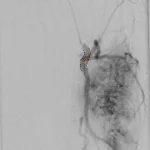

65 year old with a left femoral renal metastasis lesion. Angiograms showing vascularity of the lesion. The two annotated images show the tortuosity of the vessel supplying the lesion. The dotted orange coloured line shows the path of the vessel. It was not possible to cannulate this artery with conventional microcatheters.